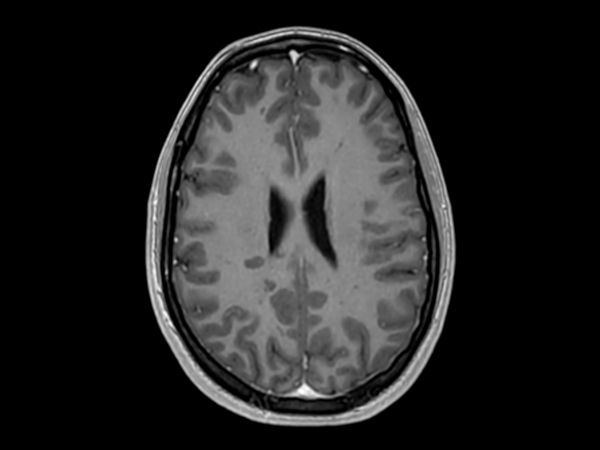

Patient with multiple brain lesions. ExamCard includes Compressed SENSE to shorten the exam time, 3D scans to acquire high resolution data in multiple directions in only one single scan and 4D-TRAK for dynamic contrast-enhanced MR Angiography enabling high spatial and temporal resolution simultaneously.

3D Double IR Compressed SENSE